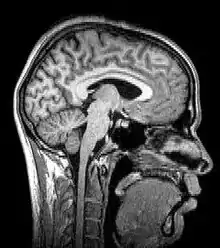

Las más modernas variaciones de la tomografía involucran la proyección de datos provenientes de múltiples direcciones y el envío de estos datos para la creación de una reconstrucción tomográfica a partir de un algoritmo de software procesado por ordenador. Los diferentes tipos de adquisición de las señales pueden ser utilizados en algoritmos de cálculo similares, a fin de crear una imagen tomográfica. Actualmente, las tomografías se obtienen utilizando diferentes fenómenos físicos, tales como rayos X, rayos gamma, aniquilación de electrones y positrones - reacción, resonancia magnética nuclear, Ultrasonido, iones y electrones. Estos se denominan: TC, SPECT, PET, MRI, ultrasonografía, 3D TEM y átomo sonda, respectivamente.

- Imagen por resonancia magnética (MRI), conocida formalmente como tomografía de resonancia magnética (MRT) o tomografía de resonancia magnética nuclear